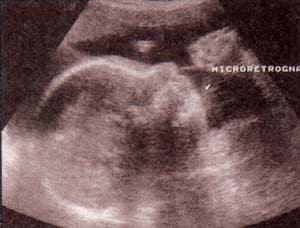

fig. 57. – (a). hallazgos ecográficos en feto con trisomía 18. perfil que ilustra microretrognatia . fig. 57.– (b). disminución en la distancia interorbitaria correspondiente a un hipotelorismo